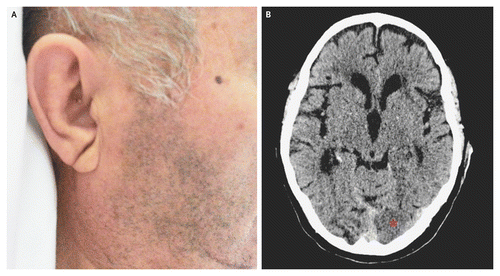

Υπάρχει όμως και ένας παράγοντας τον οποίο μπορεί να μην έχετε υποπτευθεί, και αυτός έχει να κάνει με τα αυτιά σας.

Σύμφωνα με μερικές μελέτες, το ποσό της τρίχας που έχετε στα αυτιά σας μπορεί να αποτελεί ένδειξη της μελλοντικής υγείας της καρδιάς σας. Γιατί αυτό; Μερικοί ερευνητές και γιατροί προσπαθούν να το εξακριβώσουν εδώ και δεκαετίες, και εξηγείται παρακάτω. Αφήστε κάτω τα τσιμπιδάκια και αρχίστε να ενημερώνεστε επάνω σε αυτό. Η κατανόηση του πώς οι τρίχες στα αυτιά σας συνδέονται με την υγεία της καρδιάς σας μπορεί πιθανότατα να σώσει τη ζωή σας.

Σύμφωνα με μια πρόσφατη μελέτη, υπάρχει σύνδεση μεταξύ των τριχών στο κανάλι του αυτιού και τις καρδιακές προσβολές.

Ακούγεται λιγάκι τρομακτικό, έτσι δεν είναι; Προφανώς, οι γιατροί εδώ και χρόνια έχουν παρατηρήσει μια συσχέτιση ανάμεσα στα αυτιά και την υγεία της καρδιάς.Το 1973, ο Δρ. Sanders T. Frank και η ομάδα του κατέγραψαν πως μια διαγώνια τσάκιση στο λοβό του αυτιού μπορεί να σηματοδοτεί κάποια στεφανιαία αρτηριακή πάθηση. Το 1984, μια άλλη επιστημονική ομάδα επανέφερε την ίδια θεωρία.

Το 2016 ο Δρ. Edston E. δημοσίευσε μια έρευνα στην Αμερικανική εφημερίδα της ιατροδικαστική ιατρικής παθολογίας. Δήλωνε πως η τσάκιση στον λοβό ενός αυτιού ήταν ισχυρά συνδεδμένη με καρδιακές παθήσεις σε άντρες και γυναίκες.